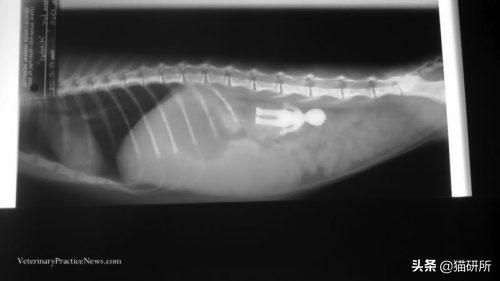

有些玩具或装饰也有较小的零件,也需要家长格外留意。虽然猫咪一般不会去特意吃掉它们,但是在玩耍时容易误食。

这只小猫因严重的厌食和反复呕吐被主人带去医院检查。X射线上识别出玩偶的轮廓,手术取出后,猫咪逐渐恢复健康。

图自:veterinarypracticenews